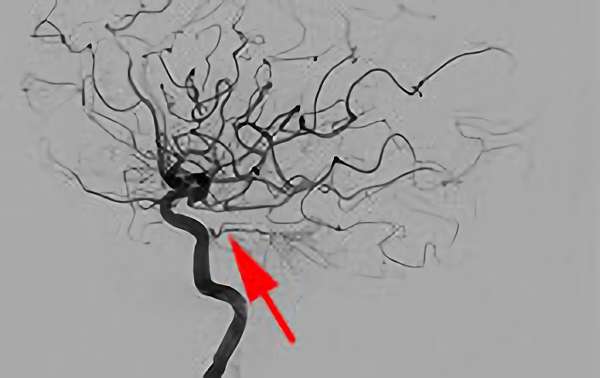

'25年4月

くも膜下出血

右内頚動脈脳動脈瘤破裂

50代

救急外来

No.1544 手術前

No.1544 手術中

No.1544 手術後